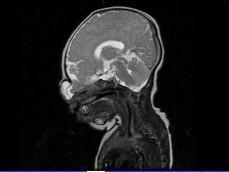

问题 出生两天的男婴,鼻根部眉间正中有一肿块,CT检查如图,请选择最可能的诊断 ( )

选项 A、鼻息肉 B、鼻咽癌 C、脑膨出 D、硬膜外囊肿 E、蛛网膜囊肿

答案 C